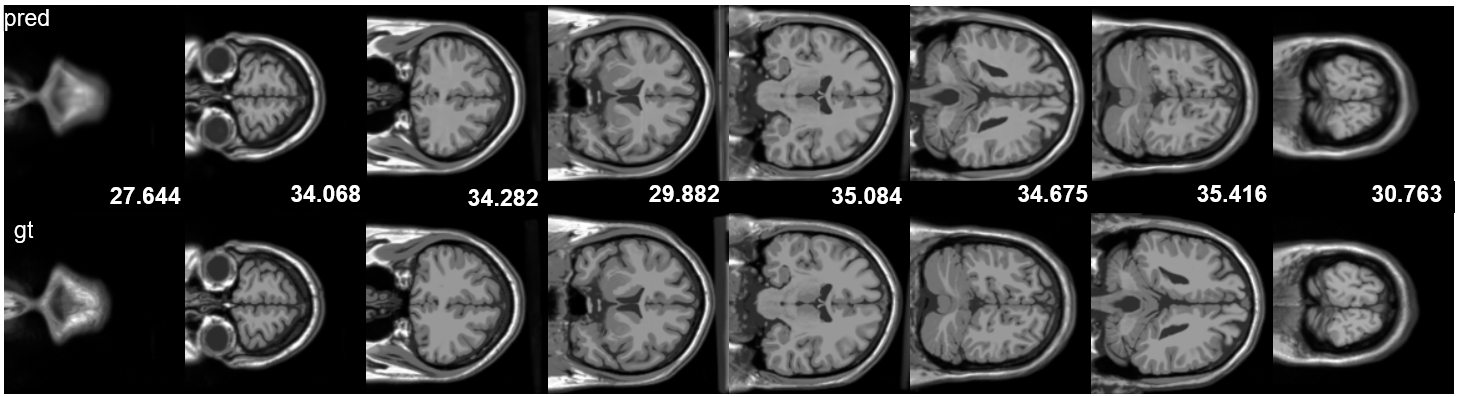

With the experimental setup described above, the reconstruction results are summarized in Table 2, and qualitative reconstruction results of axial and sagittal views are shown in Figure 2. A detailed comparison between the rendered outputs and ground truth is provided in Appendix 6. Our method successfully reconstructs fine anatomical structures, such as cortical folds and deep brain boundaries, while preserving smooth transitions in homogeneous areas like white matter or cerebrospinal fluid.

Refer to caption

Figure 2: Brain MR reconstructions in axial (top) and sagittal (bottom) views. The top row shows test set renderings with PSNR values overlaid. Red boxes highlight regions for detailed reconstruction. In each zoom-in region, the left patch is the ground truth, and the right is the prediction, with L1 errors indicating absolute differences within the region.

Figure 6 presents the reconstruction results of brain MRI images in three anatomical planes. From top to bottom, the figure shows the sagittal, axial, and coronal planes, respectively. In each set of images, the top row displays the model’s predicted images (pred), while the bottom row shows the corresponding ground truth images (gt). The predicted images are annotated with their PSNR values to quantify reconstruction quality. It can be observed that the model successfully reconstructs the brain anatomy across all planes, with clear details of gyri and sulci, and demonstrates high consistency with the ground truth in terms of contrast and structural details, indicating strong reconstruction capability.

Figure 6: Brain MR reconstructions in different anatomical planes. From top to bottom are the axial, sagittal, and coronal views, respectively.